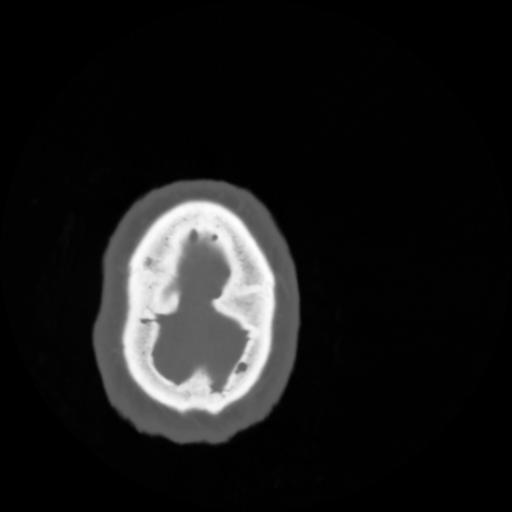

4 CEREBRO,,Vol,0.5,CEREBRO,,